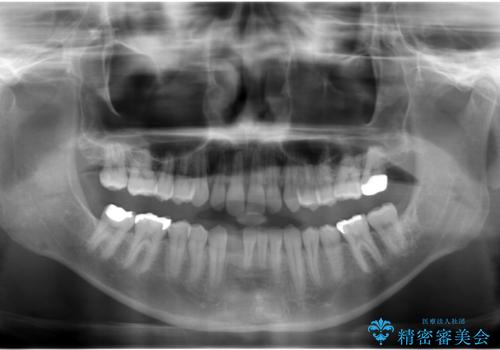

- 下の前歯が1本生まれつき少なかったため、インプラント治療を行いました。

インプラントの前に矯正治療を行い、入れる隙間を確保しました。

ブリッジにすることも可能でしたが、両側の歯が天然歯であること、また、事前に矯正で噛み合わせを整え、幅も確保していたこと、CTにより骨の厚みがある程度あったことを踏まえ、インプラントも可能であるとお話しし、選んでいただきました。

唇側の骨増成もしっかり行い、前歯部インプラントによくある、歯茎が下がって見えることもない、審美的なインプラント補綴ができました。